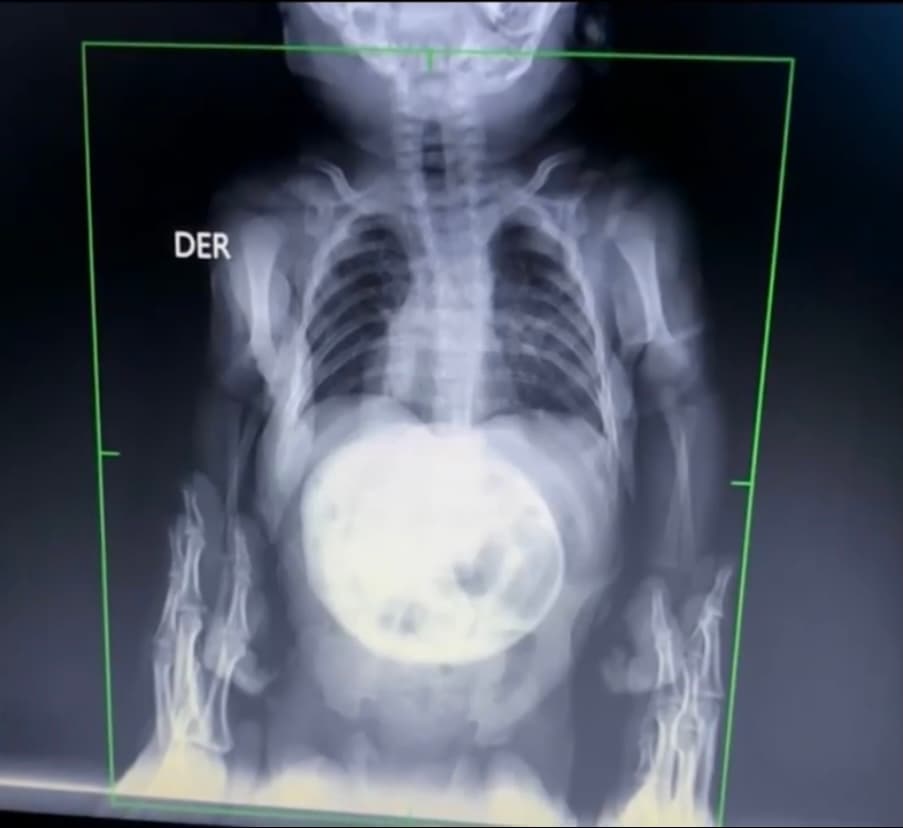

Canek Zambrano es un niño mexicano que padece de atrofia muscular espinal tipo 1, la forma más aguda de una extraña enfermedad que tiene al pequeño conectado a un respirador y no puede moverse.

El pequeño está conectado a un respirador y no puede moverse. Los médicos creen que tiene una expectativa de vida de dos años si no se le suministra un medicamento que cuesta 2 millones de dólares.

Algunos médicos le han dicho a los padres que se prepararen para lo peor porque los que padecen dicha enfermedad mueren antes de los 2 años.

Finalmente, un especialista les dijo que existía un medicamento capaz de curar esa enfermedad, pero cuesta 2 millones de dólares.